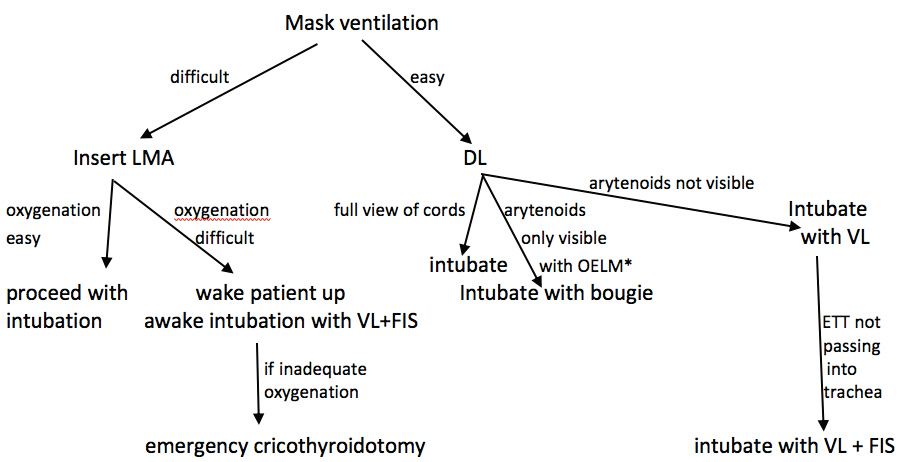

New airway devices have recently become available and anesthesia care providers need to become facile with their use. Given the difficulty of adequately predicting a difficult airway pre-operatively, the ready availability of these devices in the operating room is very important. Having this equipment on standby in the operating room is of greater benefit than a thorough preoperative airway evaluation when the aim is to avoid airway disasters. Advanced airway devices should be used early and repeated attempts at direct laryngoscopy should no longer be employed. When contemporary airway equipment is available in the operating room, blind intubation should no longer be performed. Esophageal intubation is not harmless even when recognized quickly and should be avoided. Visualization of the vocal cords during intubation will not only eliminate esophageal intubations but also reduce trauma to the vocal cords that is likely to occur during the intubation of patients with an anterior airway. The combined use of a VL with a FIS is a useful technique when the ETT cannot be passed with the standard stylet for the VL. The combined technique can be used for both asleep as well as awake FSI. These airway techniques should be taught to residents and all other anesthesia staff in simulation centers to ensure that they can be performed expeditiously when a difficult airway is encountered. Simulation centers have been demonstrated to provide an effective training platform for this. During any case of difficult airway management, the anesthesiologist should be prepared to rapidly progress to a cricothyroidotomy if this should become necessary and a capnograph should be available to confirm tracheal placement (Figure 10). Careful judgement is also necessary when extubating a patient with a difficult airway. Respiratory depressant drugs like opioids should be used sparingly or avoided altogether and neuromuscular blocking drugs should be fully reversed. Advanced airway equipment should be in close proximity to enable rapid re-intubation if this should become necessary. It is likely that the proactive use of advanced airway equipment will reduce the incidence of airway disasters in the future.

Figure 10: Airway management flowchart.

OELM: Optimal external laryngeal manipulation; DL: Direct laryngoscopy; LMA: Laryngeal mask airway; VL: Video laryngoscopy; FIS: Flexible intubation scope.